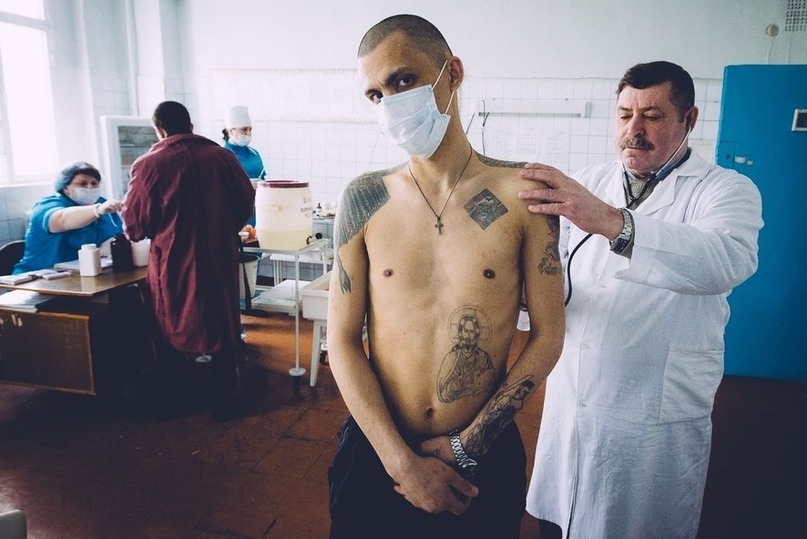

Современные методы лечения туберкулеза

Раздел: Мир в картинках